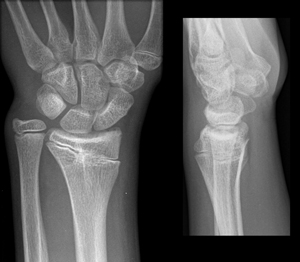

مادلانگ دفورمیتی نوعی اختلال رشد مچ دست است که موجب قوسی شدن استخوان رادیوس یا زند اعلی و برجسته شدن انتهای پایینی استخوان اولنا و پشت مچ دست و انحراف مچ دست به سمت پایین میشود .

علت بیماری به درستی شناخته شده نیست ولی میدانیم که با مختل شدن رشد در قسمت قدامی مچ دست و وجود یک نوار بافتی محکم بنام Vicker’s ligament در مفصل مچ دست همراه است. این بیماری معمولا ارثی است و در دختران نوجوان بیشتر دیده میشود و معمولا دو طرفه است. گاهی اوقات ضربه به مچ دست و یا عفونت های مچ دست میتوانند با ایجاد اختلال در رشد قسمتی از صفحه رشد پایینی استخوان رادیوس این بیماری را ایجاد کنند .در این بیماران سطح مفصلی استخوان رادیوس به سمت اولنار انحراف پیدا کردن و قوس استخوان رادیوس افزایش پیدا میکند.

مادلانگ دفورمیتی بیشتر در دختران نوجوانی تشخیص داده میشود که معمولا به علت درد و محدودیت حرکتی و تغییر شکل مچ دست به پزشک مراجعه میکنند. این بیماران وقتی ساعد خود را بصورت افقی طوری میگیرند که کف دست به طرف زمین باشد دستشان پایینتر از سطح ساعد آنها قرار گرفته است. معمولا سطح پشتی مچ دست آنها برجسته تر از معمول است و محدودیت حرکات مچ دست بخصوص محدودیت در سوپینیشن و اکستنشن و انحراف مچ دست به سمت رادیال دارند .

درمان بصورت انجام عمل جراحی است و جراحی تاثیری بر روی محدودیت حرکتی مچ دست ندارد. دو نوع درمان جراحی برای این بیماران انجام میشود. کوتاه کردن استخوان رادیوس و یا بلند تر کردن استخوان اولنا و یا هر دو آنها با هم . انحراف مچ دست بصورت جابجایی به سمت پایین و برجسته بودن انتهای پایینی استخوان اولنا از علائم دفورمیتی مادلانگ است.